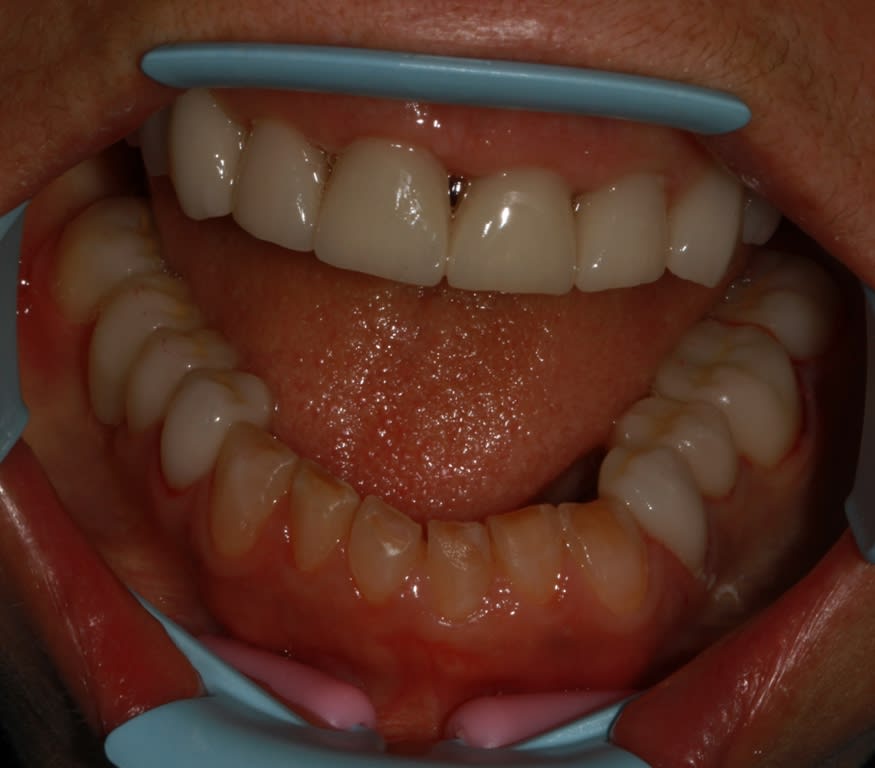

pxav

02/03/2018 à 14h31

la suite, pose des secteurs molaires prémolaires mandibulaire

Img 6138 r05rky - Eugenol

Img 6140 ec1slt - Eugenol

Img 6142 qhyptd - Eugenol

Img 6144 mwluw6 - Eugenol

enlaye

02/03/2018 à 17h48

putain ,ç est beau !!!

photo de l'arcade du haut :

j'aime beaucoup la forme d’hélice ( monzon wilson)

tu as diminué le verrouillage secteur 1

tu as aussi écarté l'axe des sillons principaux

tu as encore relevé la dvo

les adaptations gingivales sont hyper propres

t'y a bossé . là .